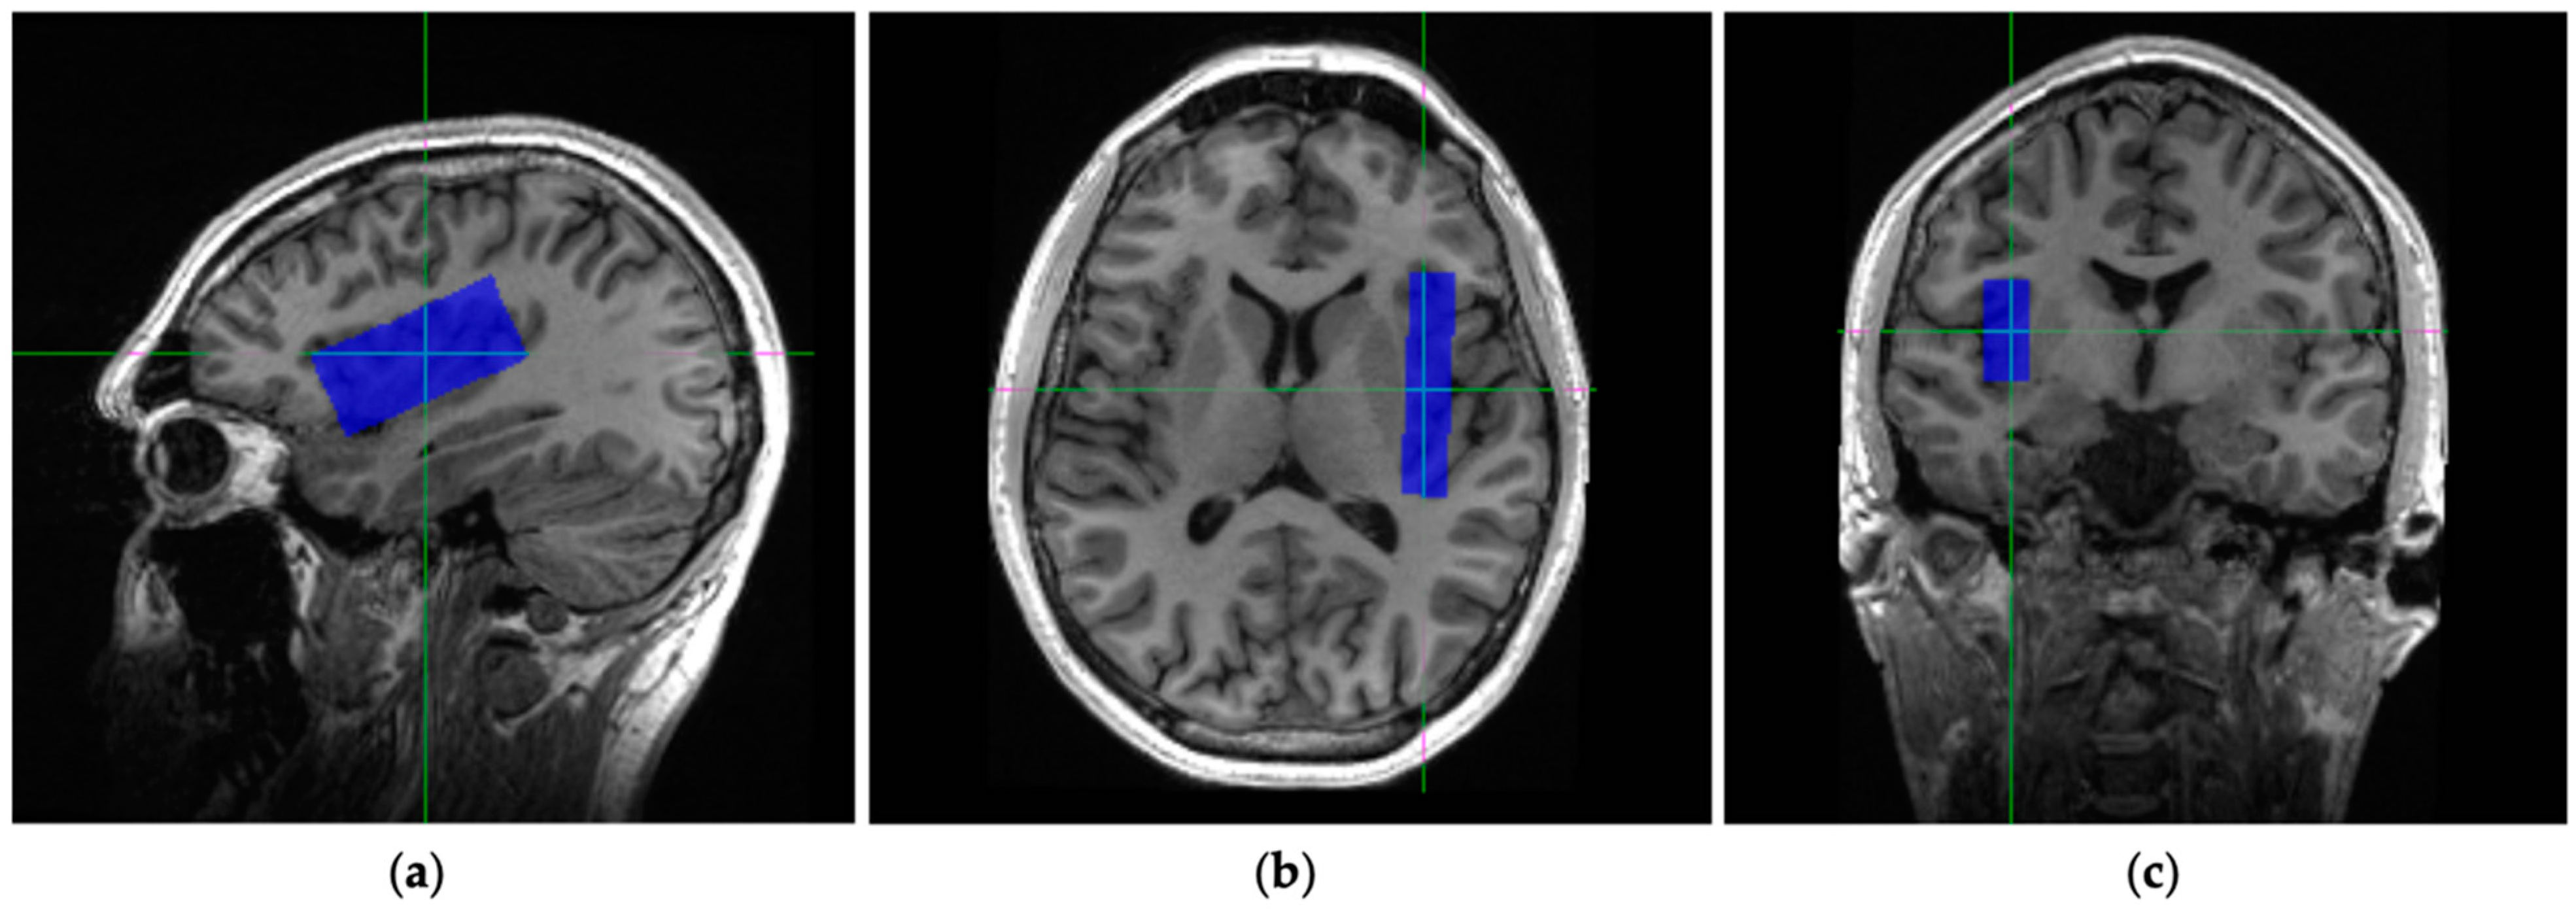

2.2. Scanning Procedures